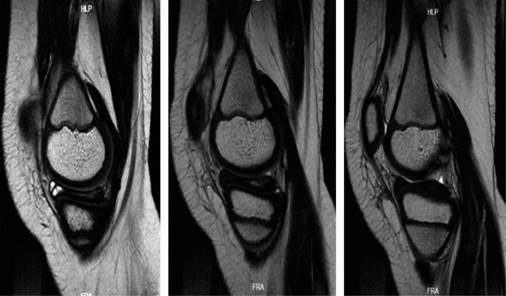

Se solicitó una resonancia magnética simple de la rodilla, que reveló una lesión de grado 3 en el menisco medial, bursitis suprarrotuliana y edema en los tejidos blandos de la parte anteromedial de la rodilla. Además, se identificó una lesión en el menisco medial con una morfología aparentemente discoidal, indicada por la presencia del «signo del corbatín» (Figuras 1 y 2).

Figura 1: Cortes sagitales de resonancia magnética de rodilla derecha en secuencia T2 en los que se observa «bow tie sign» o signo del corbatín en tres cortes consecutivos de menisco discoide medial.